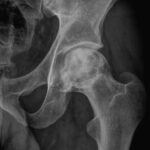

[doctormodu]1 avascular necrosis of femoral

08 대퇴골두 무혈성괴사 Avascular necrosis of femoral head, AVN